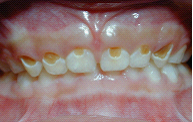

※誠樂提供多位專業醫師協助,各個療程因個人需求、狀況而有不同,皆致力達到完美需求※ 奶瓶型齲齒是指寶寶常因喝奶有飽足感而容易熟睡,睡著了還含著奶瓶,由於寶寶的吞嚥習慣是將舌頭往前往上頂,因此未吞下的牛奶都含在上顎,造成上顎前牙長期浸泡在 ...